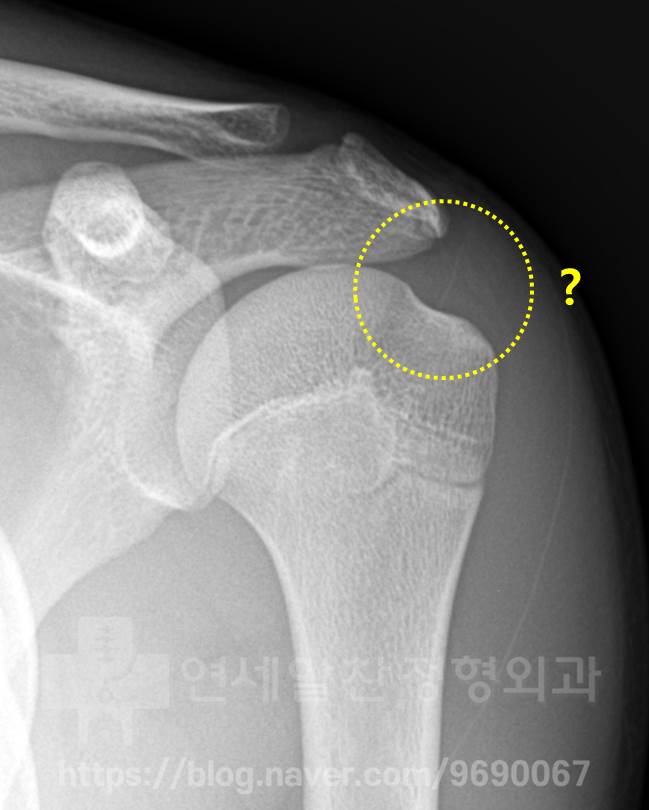

어깨관절와순 파열 없어도 물혹 제거 수술 해야할까?

어깨 물혹 있을 땐 수술로 제거 하는 것이 좋다 생각하는 분들 계신데요. 어깨관절와순 파열 같은 문제가 ...